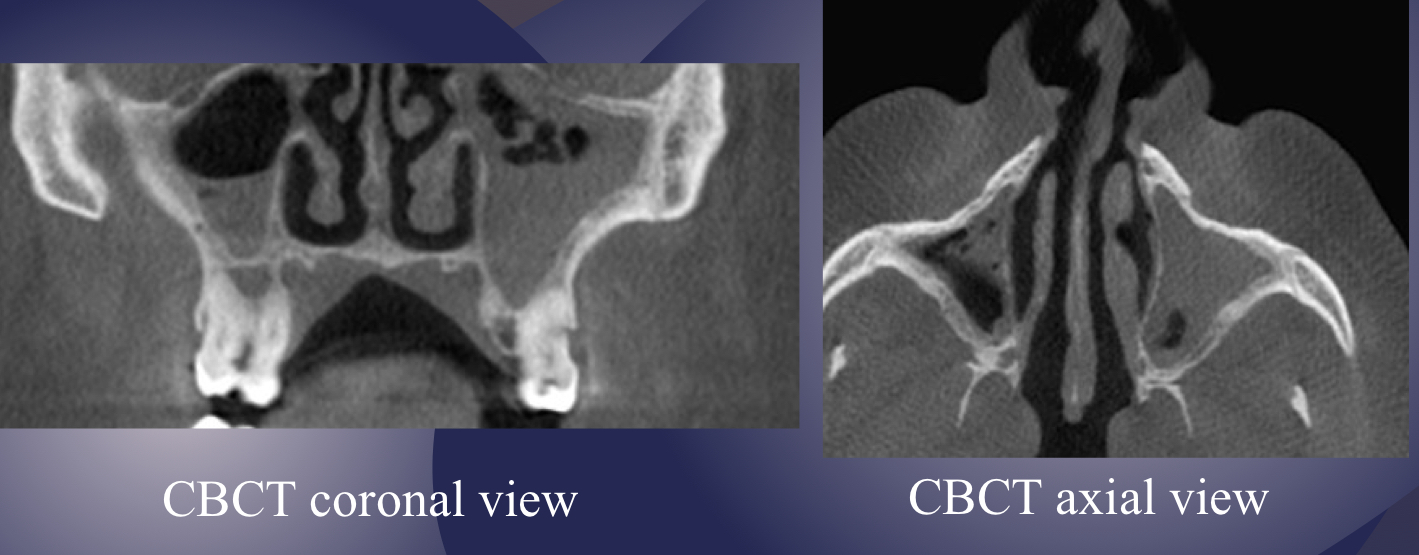

which imaging is method of choice for seeing internal structure (sequestrea) of acute osteomyelitis?

CT/CBCT